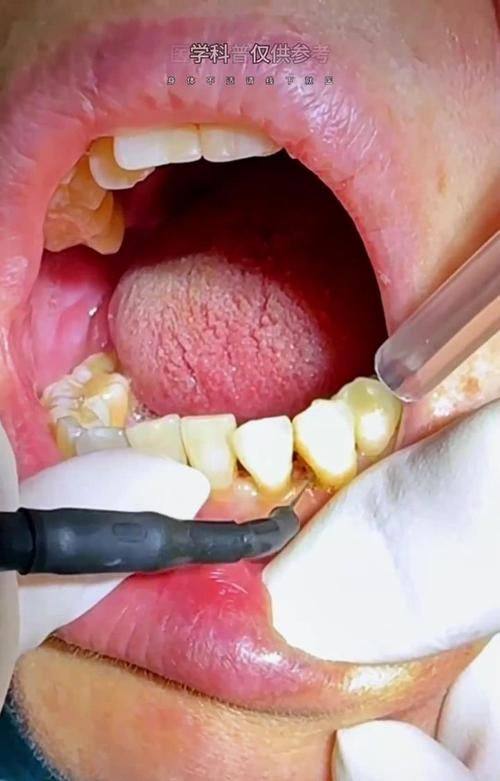

咿呀口腔门诊(光谷店)特色项目及技术优势

1. 疑难种植中 心:突破传统种植牙对牙槽骨条件的限制,根据国人牙槽骨条件研发即刻种植即刻负重技术,能轻松解决半口/全口缺牙问题,患者当天种植当天即可享受美食。